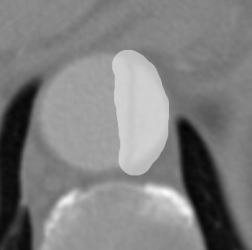

Figure 9 shows axial CTA images of an aortic dissection case. In both rows of this figure an example for executing an inpainting with the inpainting tool is given. The image section of all sub-figures is equal to the defined region of interest. The sub-figures in Figure 9 show from left to right: unedited CTA scan showing the aorta and surroundings, the mask used for the inpainting and the inpainting result. The Sub-images (a) and (b) include a dissected aorta, whereas the dissection is removed in the sub-images (d) and (f).

Refer to caption

(a) Original image

(b) Masked image

(c) Inpainting result

(d) Original image

(e) Masked image

(f) Inpainting result

Figure 9: Two examples for an inpainting of an aortic dissection utilizing the inpainting tool.

Looking at the results presented in Figure 9, one can see that the depicted dissected aorta is successfully changed to a healthy looking aorta. But it is also noticeable, that the region reconstructed by the inpainting is slightly blurred, which could be addressed by refinement of the EdgeConnect model. The timing analysis in section 6 shows that a call of the inpainting tool is completing in around four seconds, wherein the majority is caused by executing the neural network. This indicates the code of the inpainting tool itself offers little room for speeding up the application.